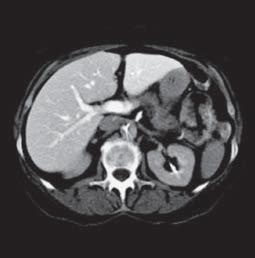

Kazuistika I (segmenty jaterní tkáně)